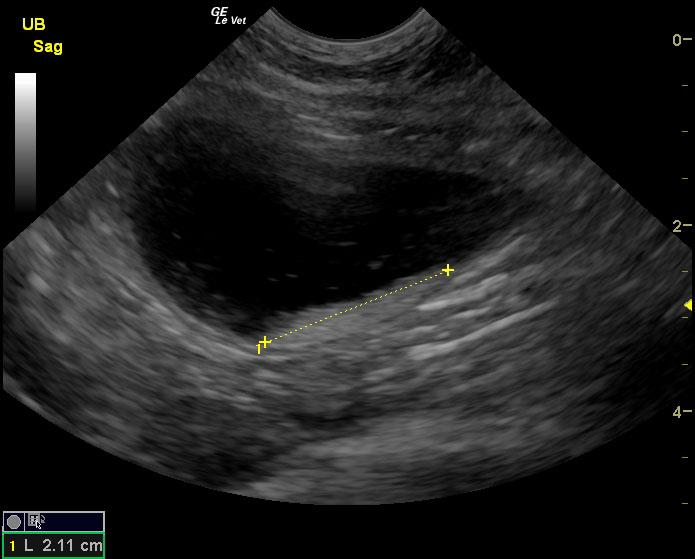

A 6-year-old SF DSH cat was presented for evaluation of chronic cystitis that was non-responsive to antibiotic and Adequan therapy. Both urinalysis and urine culture were within normal limits.

A 6-year-old SF DSH cat was presented for evaluation of chronic cystitis that was non-responsive to antibiotic and Adequan therapy. Both urinalysis and urine culture were within normal limits.